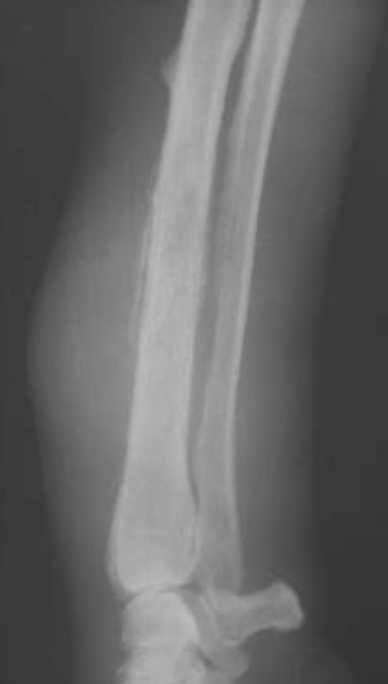

Proximal tibial

osteosarcoma with amorphous bone

formation seen lateral to the proximal fibula. A solid periosteal reaction (Codman’s triangle, arrowed) is present on the lateral cortex of the proximal tibial diaphysis.